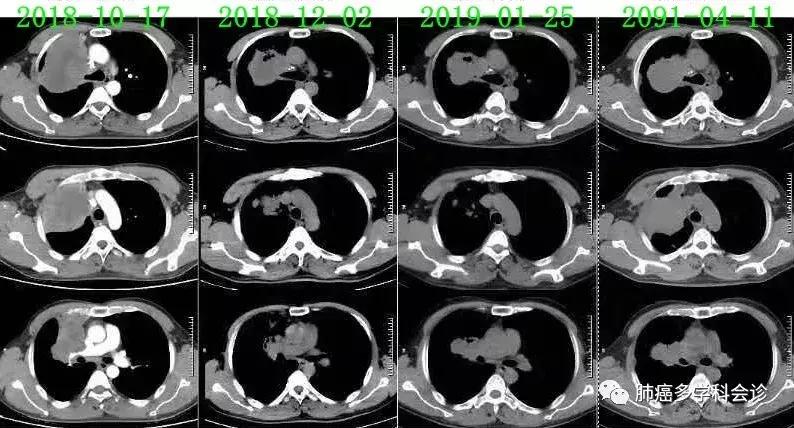

2018.10.28 - 2019.03.22,在呼吸科接受一线化疗:“吉西他滨+奈达铂”× 6周期,最佳疗效PR。2019-04-11复查CT,示疾病进展:

2019.4.12复查CT示病情进展,二线“多西他赛+奈达铂”化疗1周期。2019.5.8复查CT,提示病情稳定。患者不能耐受继续化疗。